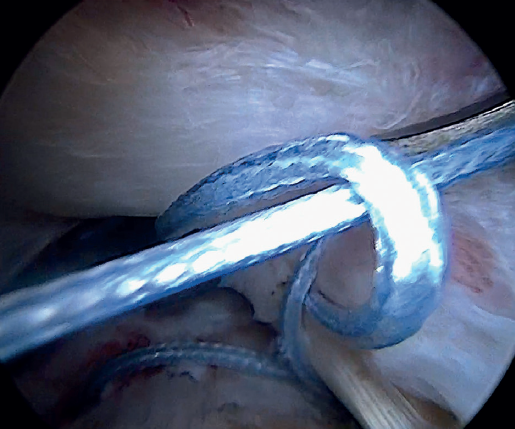

Having passed both the anterior and the posterior sutures, we proceed to knot, through the lateral portal with a working cannula, each of the sutures, starting posterior and ending anterior.

Finally, the anterolateral supraspinatus threads are used in combination with the posterolateral tapes to establish a more lateral double row with two direct anchorings that allow the threads to be threaded through two loops(Biocomposite SwiveLock® C 4.75 × 19.1 mm, Arthrex, Naples, FL, USA). This achieves a tension-free double row repair of the supraspinatus, covering the superior capsular repair made with the LPB (Figure 11).